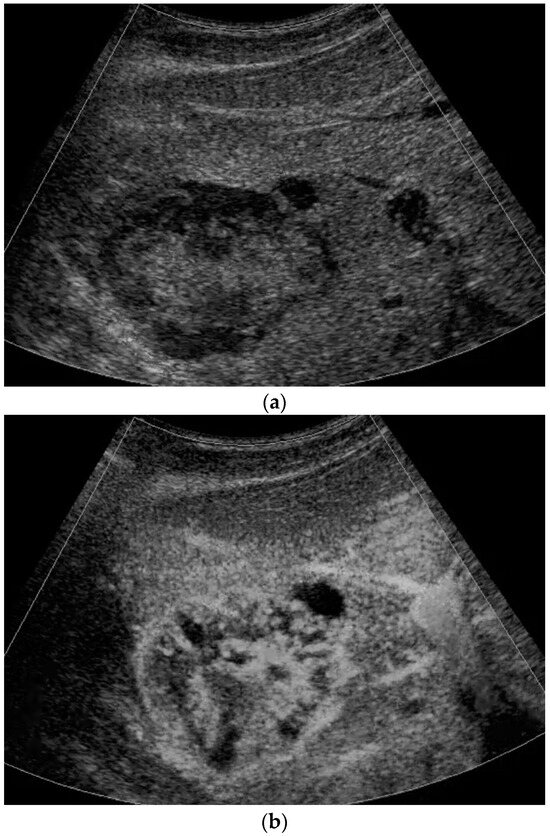

Figure 1.

A 16-year-old boy, athletic, soccer player, complaining of pain in the right lumbar–gluteal region for 10 months. MRI showed a large mass in the right iliac bone with protrusion to the muscles. Biopsy result is Ewing sarcoma. This mass is clearly visible on ultrasound (a). In liver B mode ultrasound revealed several foci: 26 × 23 mm echogenic with some hypoechoic rim (b) and entering vessel on Power Doppler mode (c) and 15 mm hypoechoic cystic-like (d). CEUS exam showed rapid filling (e) with early washout in the middle of the arterial phase (f). Washout progresses in the portal venous (g) and late venous phases (h). Liver metastases of Ewing sarcoma diagnosed. (SC5-1U transducer).